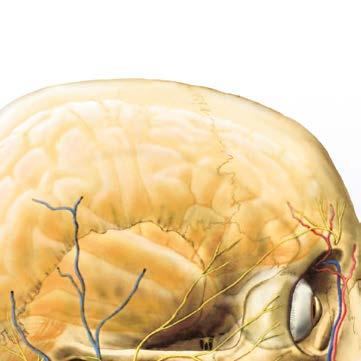

Pro didaktickou koncepci knihy platí vše, co bylo řečeno v předmluvách k prvnímu i druhému vydání prvního i druhého dílu Anatomie. V oddílu centrálního nervového systému byl navíc ještě volen další postup, a to probrání celého systému třikrát, ve třech navazujících fázích. V první fázi je probrána makroskopika CNS, včetně horizontálních a frontálních řezů, aby se student seznámil se všemi základními útvary a pojmy a byl s to orientovat se na materiálu v praktických cvičeních. Ve druhé fázi jsou detailněji probrány útvary šedých a bílých hmot v jednotlivých oddílech CNS, zejména jádra a jejich funkční význam. Ve třetí fázi jsou tyto útvary propojeny nervovými dráhami podle skupin funkcí, které jsou těmito dráhami zajišťovány. Právě při studiu CNS má spojení morfologie struktur s jejich funkcí mimořádný význam a jen tak je možné pochopit celý tento složitý systém. Obrazy ke třetímu dílu Anatomie vytvořil akad. malíř Ivan Helekal, jemuž se v průběhu práce podařilo najít ideální kompromis mezi realistickým zobrazením a potřebným didaktickým zjednodušením obrazu, který se tak pro studenta stává přijatelným a zapamatovatelným. Děkuji mistru Helekalovi za výborné kresby a za vynikající spolupráci. K doplnění obrazového souboru a pro připomenutí tradic ústavu byly použity čtyři obrazy, které v Anatomickém ústavu v minulosti vytvořili prof. MUDr. RNDr. Ladislav Borovanský, DrSc., a vynikající vědecký kreslíř ústavu, pan Stanislav Macháček. Mikrofotografie v kapitole Molekulární aspekty vývoje nervového systému zhotovil prof. MUDr. Miloš Grim, DrSc., a obr. 144/2, 3 a 310/3 nakreslil Mgr. Jan Kacvinský.